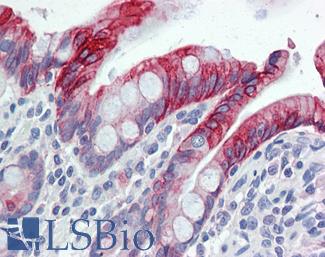

CK20 (KRT20)

Anti-KRT20 / Cytokeratin 20 antibody IHC of human small intestine. Immunohistochemistry of formalin-fixed, paraffin-embedded tissue after heat-induced antigen retrieval. Antibody LS-B5959 dilution 1:50. This image was taken for the unconjugated form of this product. Other forms have not been tested.